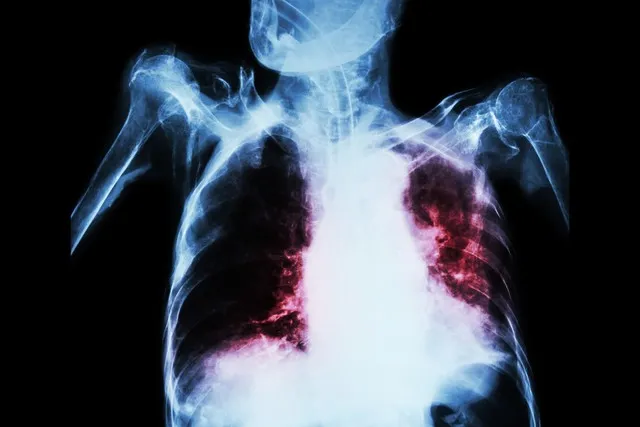

胸片和CT是两种常见的医学影像检查方法,它们在诊断疾病方面各有优势。胸片是一种传统的二维平面成像技术,而CT则是先进的三维断层扫描技术。这两种检查方式在临床应用中扮演着重要角色,但它们之间存在显著差异。

胸片检查快速、简便且经济,通常只需不到半秒钟就能完成。它能清晰地显示胸部的大体病变,如肺炎、肺气肿、肿瘤等。胸片检查的辐射剂量相对较低,一次普通的X光胸片辐射量约为0.02msv。这种检查方式特别适合用于初步筛查和定期体检。

相比之下,CT扫描能够提供更为详细和精确的三维图像。它通过连续的断面扫描,可以清晰地显示人体内部组织的密度分布。CT检查在诊断肌肉和骨骼疾病、定位肿瘤、指导手术等方面具有独特优势。然而,CT检查的辐射剂量相对较高,一次普通CT的辐射量在2~15msv之间,是胸片的几十倍。